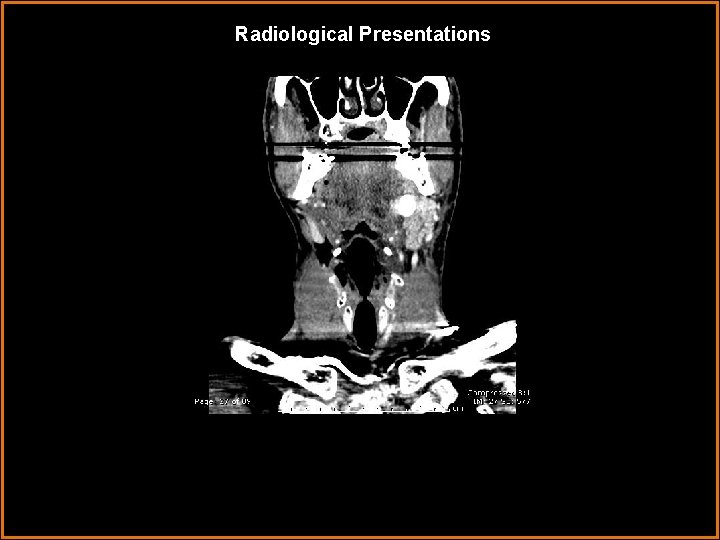

Radiological Presentations

Findings and Differentials Findings: Markedly enlarged, enhancing left submandibular gland with a large 1. 1 cm stone in Wharton’s duct. Differentials: • Submandibular venous vascular malformation – lobulated, heterogenously enhancing mass. • Sialosis – painless bilateral enlargement of salivary glands, usually the parotid glands. Associated with diabetes, obesity, and alcoholism. • Kuttner tumor – pseudomass of salivary gland associated with calcification.

Diagnosis Sialadenitis caused by sialolithiasis.